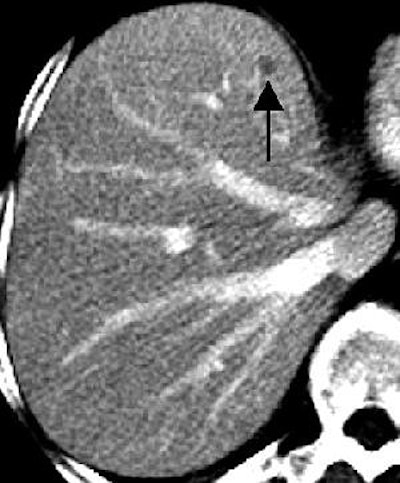

| Transverse contrast-enhanced helical CT scans of the abdomen in a 70-year-old woman with infiltrating ductal carcinoma (stage IIA at initial presentation) and hepatic cysts. Above, baseline scan obtained with 7-mm-thick sections shows a hepatic lesion (arrow) deemed TSTC. Below, follow-up scan obtained with 7.5-mm-thick sections 11 months later shows that the hepatic lesion (arrow) has increased in size -- from 17 x 10 mm to 20 x 10 mm. A second hepatic lesion (not shown) showed a similar increase in size -- from 3 x 3 mm to 5 x 5 mm. Subsequent MR imaging of the abdomen revealed the presence of hepatic cysts, but no hepatic metastasis. Figure 3AB, Hanan KI, Patterson SA, Panicek DM, "Hepatic Lesions Deemed Too Small to Characterize at CT: Prevalence and Importance in Women with Breast Cancer," Radiology 2005; 235:872-878. |